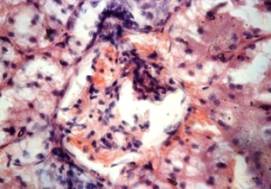

В

гистологических срезах почек выявлено выраженное утолщение коркового вещества. Вследствие гипертрофического

разрастания волокнистой соединительной

ткани структура строения этой

области органа была умеренно сохранена. Отмечалась плохая сохранность

просветов канальцев. Почечные тельца отличались резким расширением полости капсулы

клубочка. Сосудистые клубочки

оттеснены в сторону артериол. В них отсутствовали просветы капилляров. В

отдельных клубочках разрежены

мезангиоциты и эндокриноциты.

Атрофические процессы с явлениями

некробиоза наблюдались в эпителиальных клетках большинства извитых

канальцах (рис.1).

Рис

1. Атрофические, склеротические и некробиотические изменения почечного тельца

кота 20 летнего возраста. Окраска гематоксилином и эозином. Х240.